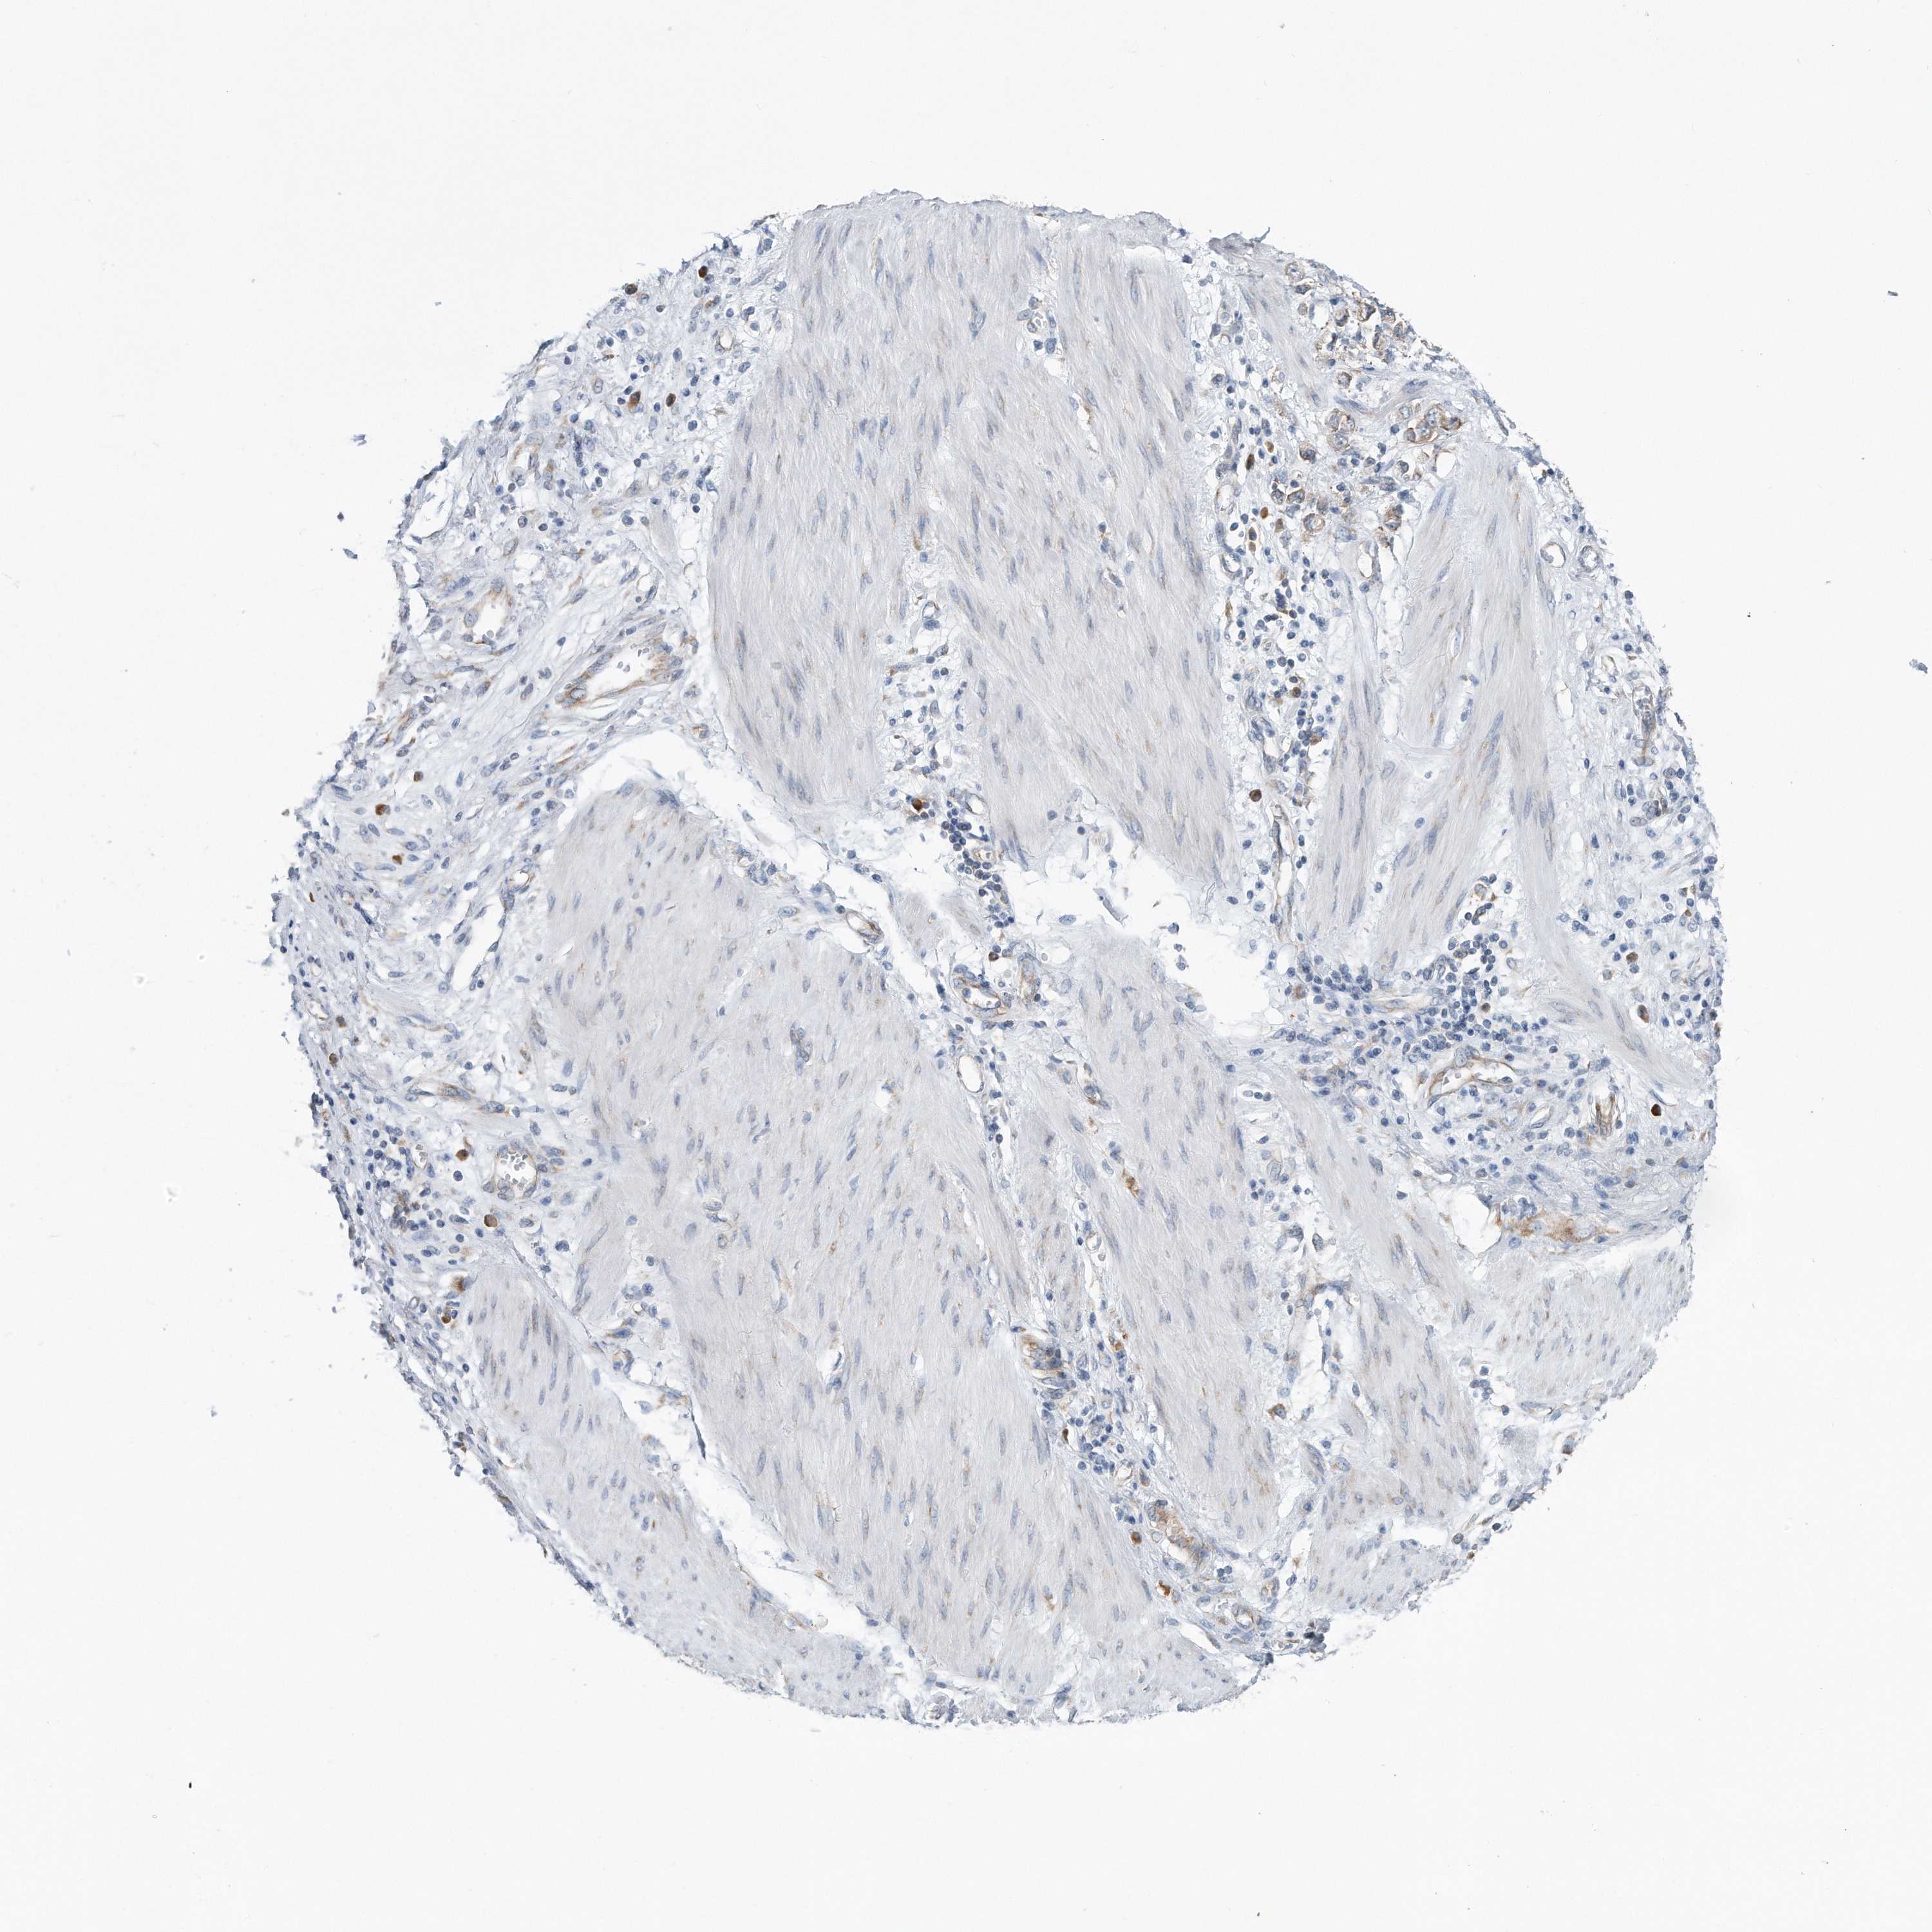

STOMACH CANCER - Protein expressioni

A mouse-over function shows sample information and annotation data. Click on an image to view it in a full screen mode. Samples can be filtered based on level of antibody staining by selecting one or several of the following categories: high, medium, low and not detected. The assay and annotation is described here.

Note that samples used for immunohistochemistry by the Human Protein Atlas do not correspond to samples in the TCGA dataset.

Antibody stainingi

Antibody staining in the annotated cell types in the current human tissue is reported as not detected, low, medium, or high, based on conventional immunohistochemistry profiling in selected tissues. This score is based on the combination of the staining intensity and fraction of stained cells.

Each image is clickable and will lead to virtual microscopy that enables deeper exploration of all samples and also displays staining intensity scores, fraction scores and subcellular localization as well as patient and tissue information for each sample.

Staining

High

Medium

Low

Not detected

Intensity

Strong

Moderate

Weak

Negative

Quantity

>75%

75%-25%

<25%

None

Location

Nuclear

Cytoplasmic/membranous

Cytoplasmic/membranous,nuclear

Adenocarcinoma, NOS